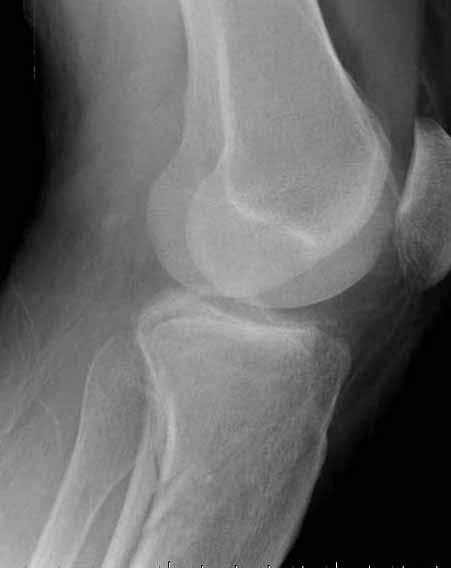

Двухколоннный перелом тибиал плато с вовлечением проксимального диафиза. Внутрисуставной компонент без смещения, и такой перелом можно лечить любым из описанных методов, о которых говорят наши коллеги.

Удобно аппаратом Илизарова или интрамедуллярным гвоздем. Гвозди не так сложно, как пугают, тем более Александр готов помощь с методичкой. Сперва надо установить компрессирующие шурупы на мыщелки. Давно отказались в пользу 3.5-4.0 мм кортикальных вместо толстых спонгиозных, потому что не доказаны преимущества толстых шурупов. Тонкие шурупы в субхондральной зоне смотрятся намного элегантнее, чем толстые 6.5.

Это мероприятие превращает перелом в простой диафизарный, который легко можно фиксировать гвоздем. Шурупы надо установить сзади предполагаемого места введения гвоздя.